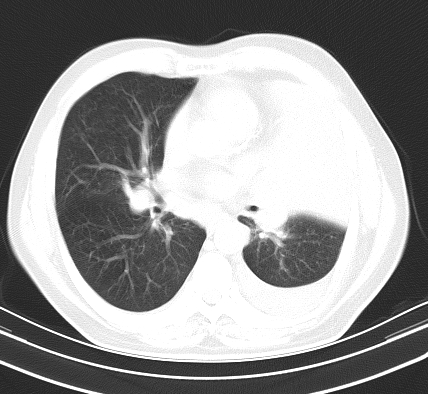

以下是引用老爱克斯新网客在2008-7-31 6:30:00的发言:[br]左肺上叶大片状病灶,左肺上叶支气管狭窄呈鼠尾状,左肺门增大,纵隔内见肿大淋巴结,左侧胸腔积液,余肺清晰。左肺中心型肺癌淋巴结转移,

以下是引用zjb在2008-7-31 6:32:00的发言:[br]左侧中心性肺癌 阻塞性肺炎 肺不张 胸腔积液 建议气管镜

以下是引用zjzjr在2008-7-31 8:45:00的发言:[br]考虑左侧中心性肺癌伴阻塞性肺炎,左肺上叶肺不张,纵隔淋巴结转移;左侧胸腔积液。建议行纤支镜检查。

以下是引用sdzyy在2008-7-31 8:47:00的发言:[br]病灶较治疗前有所进展,胸水增多, 左侧中心性肺癌 并 阻塞性肺炎 肺不张 胸腔积液 可能性大; 建议气管镜检查。 [br] [br]